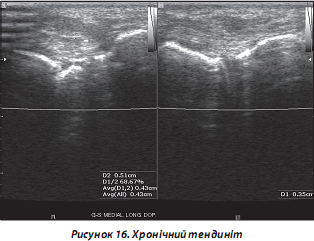

в) хронічний тендиніт: частіше спостерігається в сухожиллях надколінка, ротаторної манжети, ахілловому сухожиллі (рис. 15):

— сухожилля без СО: потовщені, ехоструктура неоднорідна, іноді наявні гіперехогенні включення — ділянки фіброзу чи кальцифікатів уздовж сухожильних волокон;

— кальцифікуючий тендиніт: виникає частіше в сухожиллях верхньої кінцівки на фоні системних захворювань сполучної тканини та метаболічних розладів (наприклад, подагра та метаболічні артропатії). При УЗД виявляються гіперехогенні включення (найчастіше — мінімальні (крапчасті), іноді — більші) в сухожиллях; останні часто потовщені (рис. 16);